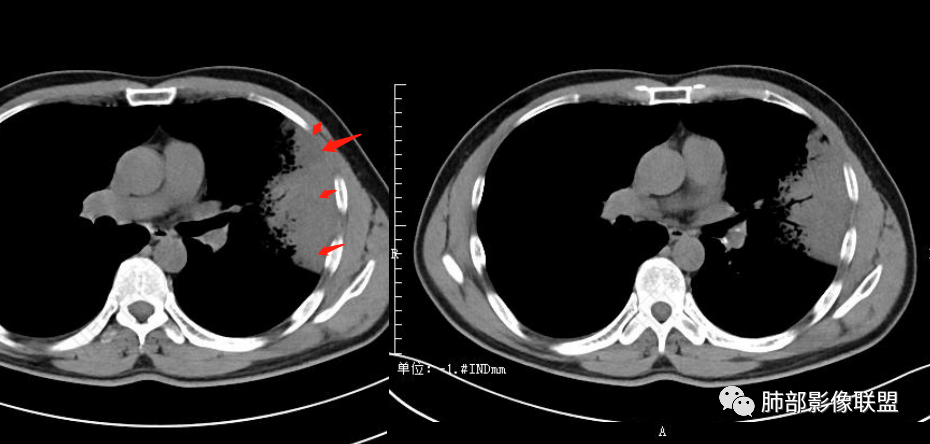

甄德强:

左肺上叶大片状实变影混合磨玻璃影,其内可见蜂窝征,增强扫描明显强化,进入病灶血管边缘有侵犯,结合病史,考虑肺炎型肺癌。鉴别诊断大叶性肺炎。

中年男性,咳嗽咳血,影像表现左肺上叶片状阴影,周围可见多发磨玻璃影,病灶内支气管僵硬,增强病灶内可见血管造影征,病灶与胸膜可见栽赃,考虑恶性病变,粘液性腺癌。

左肺上叶胸膜下实变伴周围边缘磨玻璃,其内可见枯枝征及蜂窝,不均匀强化,可见低密度影,血管显示尚可,考虑肺炎型肺腺癌

左肺大片实变,密度不均,边缘膨隆,周围磨玻璃,强化密度略低,双肺小结节,考虑粘液腺癌

左肺上叶胸膜下大片状实变区,周围散在磨玻璃影,局部膨隆,界清,近端气管截断,叶间胸膜局部稍膨隆,增强扫描实变区轻度强化,内走形血管僵硬,轮廓毛糙,胸膜栽赃,半年病史考虑恶性,粘液性腺癌

左肺上叶大片状实变密度影,边缘见磨玻璃密度,呈外向内生长,内可见多发支气管影,走行僵直,增强后实变部分明显不均匀强化,血管纤细,考虑粘液腺癌可能大

男,46岁,反复咳嗽半年,痰中带血,加重10天,左肺上叶大片状实变影,边缘模糊,病灶内见蜂窝影及僵硬支气管,双肺内见多发小结节,增强扫描,病灶明显强化,左侧胸壁增厚,考虑恶性病变,粘液性腺癌可能。

2.左肺上叶大片状混合密度影,未见空洞,实变影主要位于胸膜下,长轴与胸膜平行,实变区内部密度不均、其内可见多发小斑片状低密度影,磨玻璃影多位居肺门一侧,可见网格,磨玻璃影边界多可分辨,重力分布趋势。病灶区支气管显示较为通畅,进入外围实变区渐至消隐。病灶轻度不均匀低强化,病灶区肺动脉显示较良好,未见破坏。